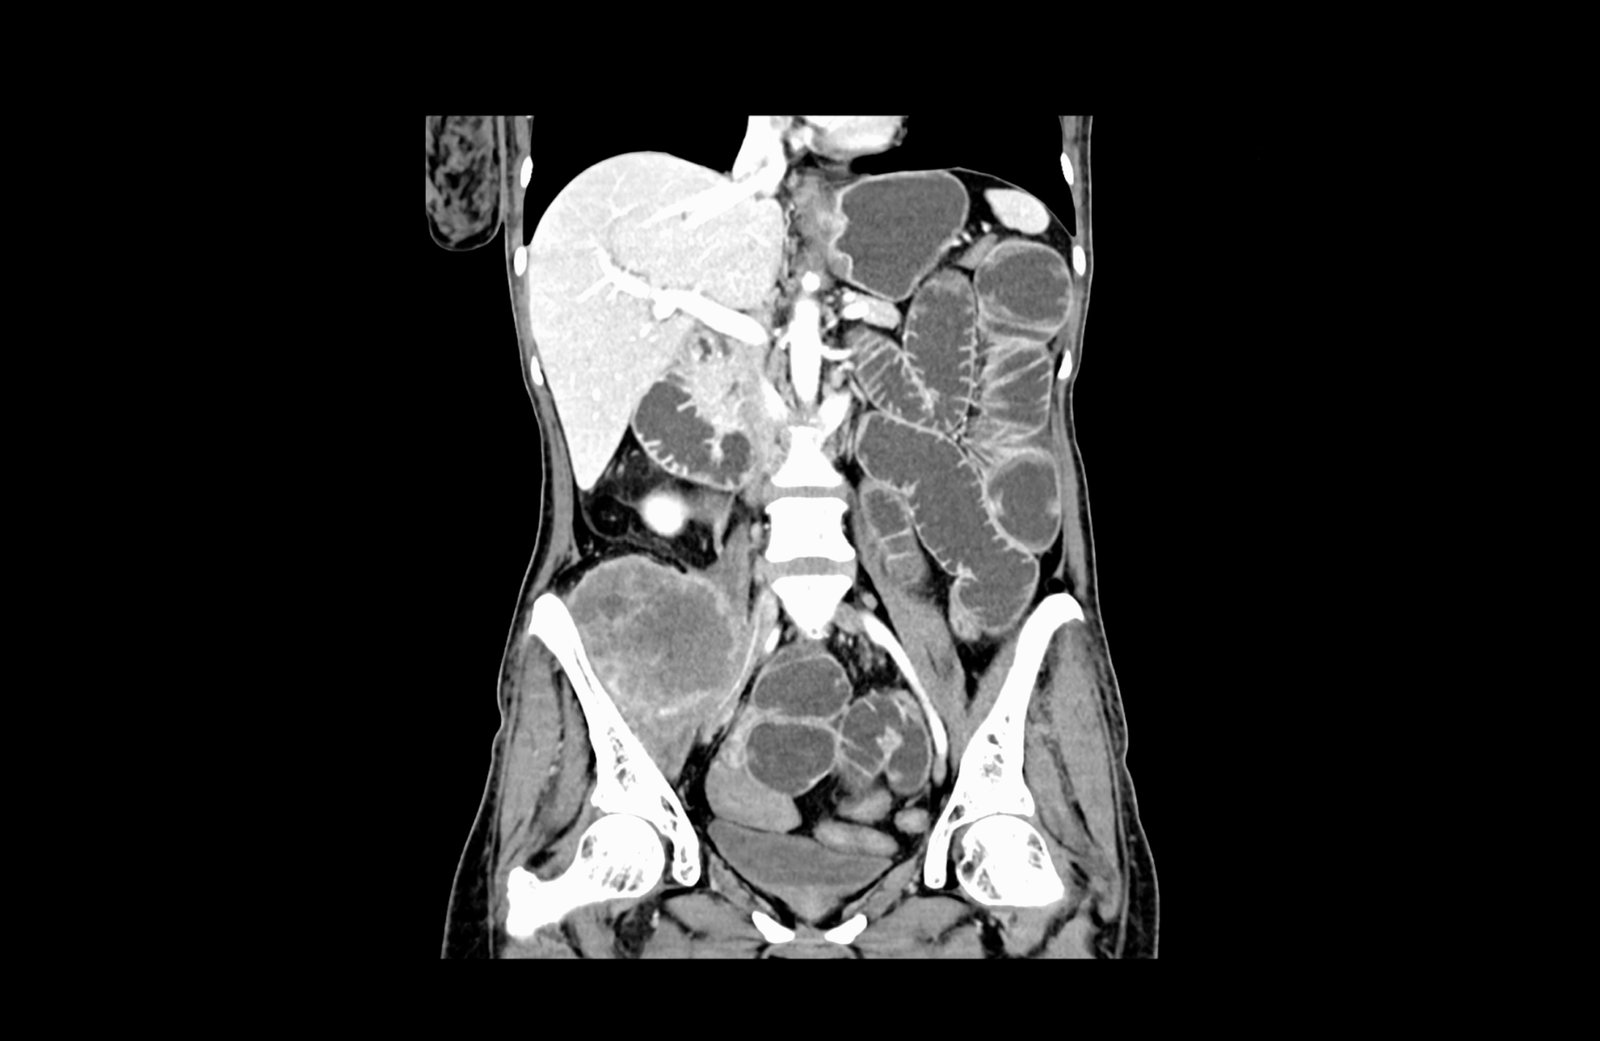

- локорегионална метастатична лимфаденомегалия обтураторно, параилиачно, ретроперитонеално до нивото на бъбречните съдове

- ангажиране на вътрешната илиачна съдова дъга

Медиална компресия и деформиране на лумените на десните общи и външни илиачни съдове. Прорастване на тумора през цялата дебелина на m. iliacus

Параилиачна лимфаденомегалия с размер на възлите до 2см.

Ретроперитонеална лимфаденомегалия, суспектна за малигнена.